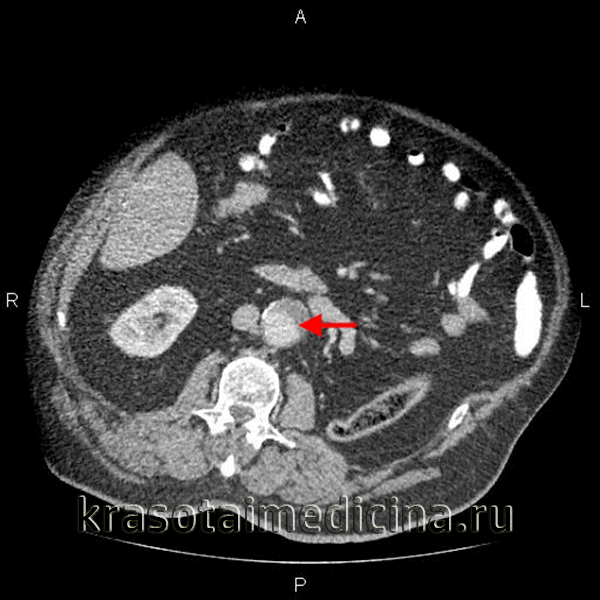

- Рентгеновская диагностика. Наиболее доступным методом диагностики аневризмы брюшной аорты служит обзорная рентгенография брюшной полости, позволяющая визуализировать тень аневризмы и кальциноз ее стенок. КТ или МСКТ брюшного отдела аорты позволяет получить изображение просвета аневризмы, кальциноза, расслоения, внутримешкового тромбоза; выявить угрозу разрыва или свершившийся разрыв. Кроме указанных методов, в диагностике аневризмы брюшной аорты применяются аортография, внутривенная урография.